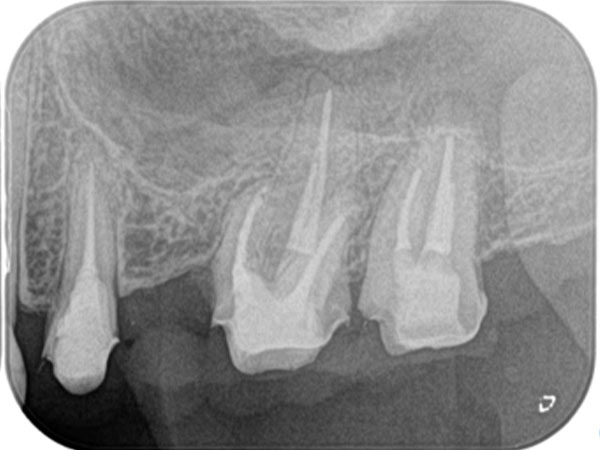

根管治療がうまくいかなかった場合、歯の根の先端に膿がたまることがあります。膿が溜まっている袋が大きいと抜歯になりますが、そうでない場合は外科的な処置で治療できることがあります。歯茎を切開して歯の根を切断し、膿の袋を摘出します。この処置を「歯根端切除術」といいます。

術前

術中

術後